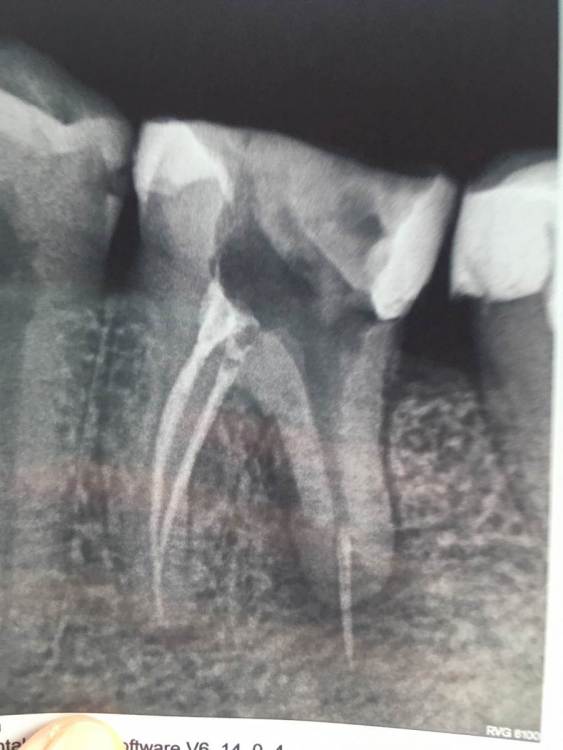

Iris11 Опубликовано 4 сентября, 2023 Поделиться Опубликовано 4 сентября, 2023 Здравствуйте. Хочется определиться. Болит зуб. Сходил на консультацию. Первый врач говорит, что зуб под удаление и имплант. Второй говорит, что можно спасти. Вскрыть вынуть штифт, пролечить, поставить новый штифт. Конечно хочется спасти, но есть ли смысл, т.к он гарантии не даёт. Помогите пожалуйста определиться. Ссылка на комментарий

red_butler Опубликовано 4 сентября, 2023 Поделиться Опубликовано 4 сентября, 2023 Здравствуйте. Если судить только по снимку, с поправкой на его плохое качество, зуб можно сохранить. Потребуется повторное лечение корневых каналов и последующее протезирование искусственной коронкой. Нужен грамотный стоматолог терапевт эндодонтист. На лечение корневых каналов гарантии нет. Если хотите гарантий, то удаление и имплантация. Ссылка на комментарий

Carioznik Опубликовано 10 сентября, 2023 Поделиться Опубликовано 10 сентября, 2023 08.09.2023 в 17:10, Iris11 сказал: почему врач оставил зуб открытым Такой метод широко применялся ранее. Сейчас так лучше (по возможности) не делать, есть более правильные методы лечения. 08.09.2023 в 17:10, Iris11 сказал: Говорит, что гной не вышел зуб нужно удалять. Не факт, но процент неудачи ближайшей или отдаленной в Вашем случае не маленький. 08.09.2023 в 17:10, Iris11 сказал: совсем никак не спасти? Можно, но сначала нужна хорошая диагностика для определения прогноза лечения, далее- врач должен обладать достаточными мануальными навыками (например, лечение под микроскопом этого зуба является важным условием: качественно запломбировать один из корней зуба без увеличения - будет ,наверное ,невозможно, но и не только в этом дело...). Ищите врача специализирующегося на лечении каналов (он будет работать с микроскопом по умолчанию). Но будьте готовы к тому, что и он может "забраковать" этот зуб либо до, либо в процессе лечения. 1 Ссылка на комментарий